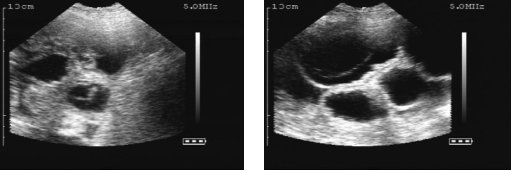

扫描配种第24天的母猪,大的胚胎囊可以很容易的看到。

Scans day 24. Large embryos bladders which are easy to see.

位置1的超声波图像.

Ultrasound image position 1.

位置2的超声波图像.

Ultrasound image position 2.

位置3的超声波图像.

ltrasound image position 3.

位置4的超声波图像.

Ultrasound image position 4

位置5的超声波图像.

Ultrasound image position 5